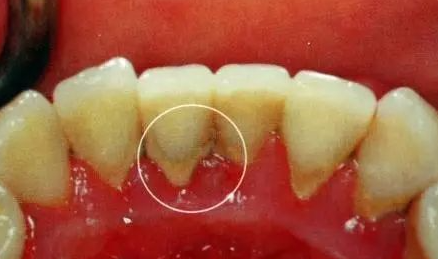

我最中意“好熱鬧啊”,每日都要去刺激下牙齦,牙齦就會發炎,有時牙齦內側仲會有潰瘍,你嘅牙齒就會出現牙齦出血、口氣唔好同牙周感染等問題。

我唔單止係一個硬漢,仲係“敵軍嘅作戰基地”,我會滋生更多嘅牙菌斑同時吸附更多嘅細菌毒素,我嘅隊伍就會愈來愈強大!經過我“日積月累”嘅努力,你就換上咗牙周病,當你嘅牙周病愈來愈嚴重!可能只可以拔咗呢顆牙齒!呢顆牙齒會係我嘅榮譽品!